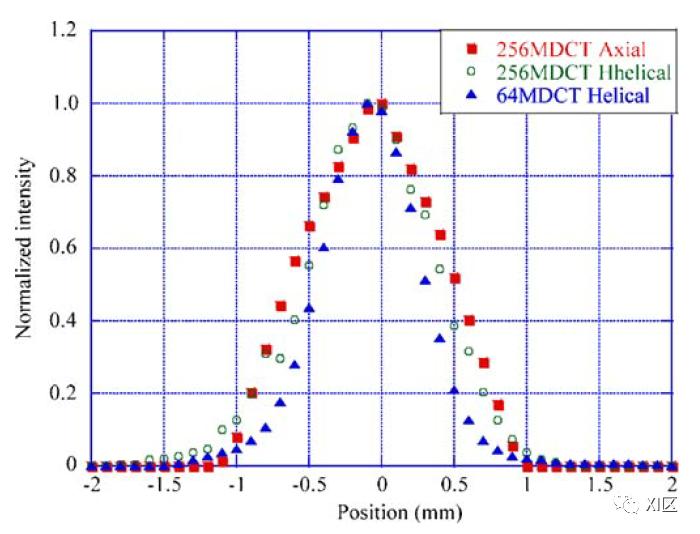

不同设备的有效层厚与标称层厚差异程度不同,标称层厚0.5 mm的256排CT和64排CT的轴扫和螺旋扫描获得的有效层厚不同。早期试验发现,256排MDCT轴扫和螺旋扫的FWHM分别为1.18 mm和0.96 mm,64排MDCT螺旋扫的FWHM为0.77 mm,比标称层厚更厚54-136%。由于焦点尺寸更小,64排MDCT的FWHM比256排MDCT更好。

Mori S , Endo M , Obata T , et al. Properties of the prototype 256-row (cone beam) CT scanner. European Radiology, 2006, 16(9):2100-2108.

针对早期使用z-sharp技术和SureView技术的CT测试发现,对于标称层厚0.6 mm,不同螺距时测试的有效层厚分别为0.66-0.69 mm;螺距是1时,标称层厚0.6 mm的有效层厚为0.66 mm。有效层厚均略大于标称层厚,但与标称层厚相比均不超过0.1 mm。测试的SSP形状近似钟形,螺距变化对SSP、有效层厚和z轴空间分辨率的影响很小*。